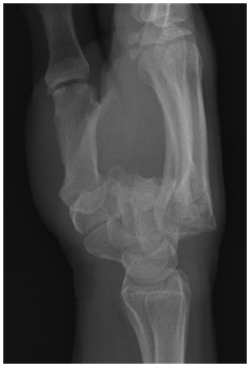

The width of the 2nd through the 5th carpometacarpal joint spaces is uniform, measuring 1-2mm. Disappearance of the CMC joint space suggest dislocation14 (Figure 3).

Figure 3 Overlapping over CMC indicates a dislocation.

Overlapping surfaces

Overlap seen at two normally parallel joint margins indicates subluxation or dislocation.14